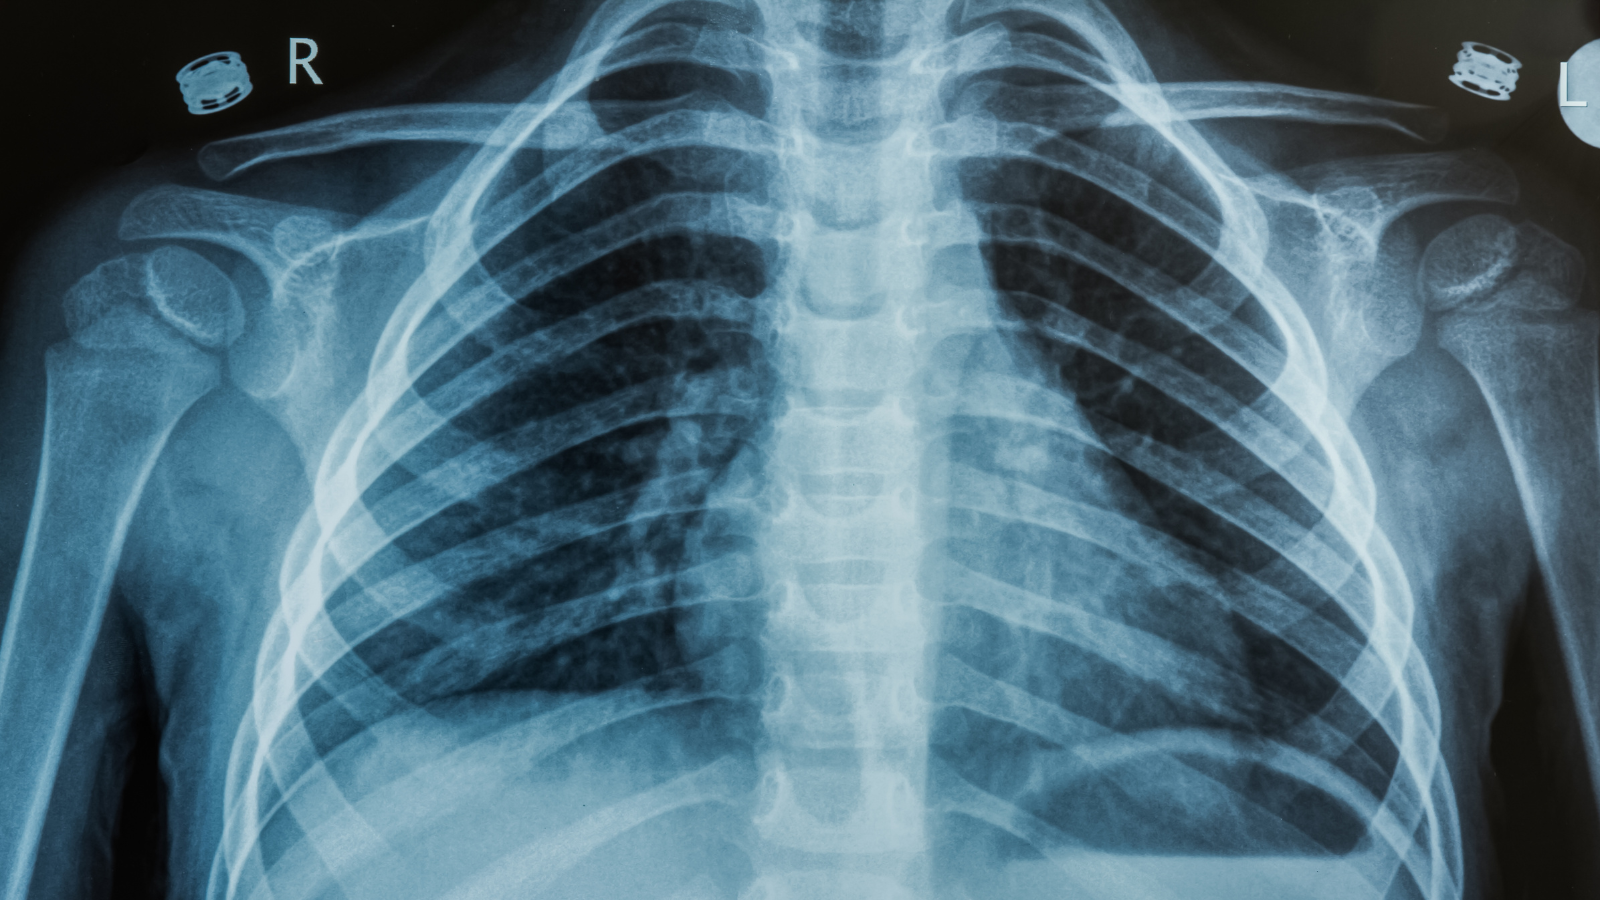

- Chụp X-quang ngực thẳng: Đây là phương pháp phổ biến nhất để xác định vị trí gãy xương sườn số 5 6 7 và kiểm tra tình trạng tràn khí/máu màng phổi.

- Chụp CT - scan lồng ngực: Giúp quan sát chi tiết các vết nứt nhỏ và đánh giá tổn thương ở phổi, mạch máu mà X-quang thường có thể bỏ sót.